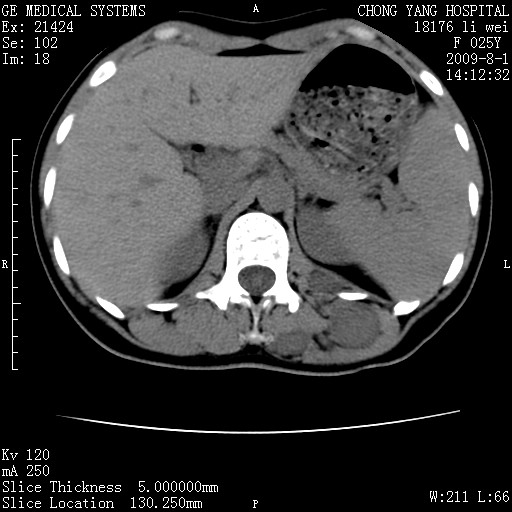

以下是引用pujunzhi在2009-8-1 20:23:00的发言:[br]胸椎旁及背部肌间良性病变,范围广,边界清,沿肌间生长,考虑淋巴管瘤、血管瘤,建议增强扫描。